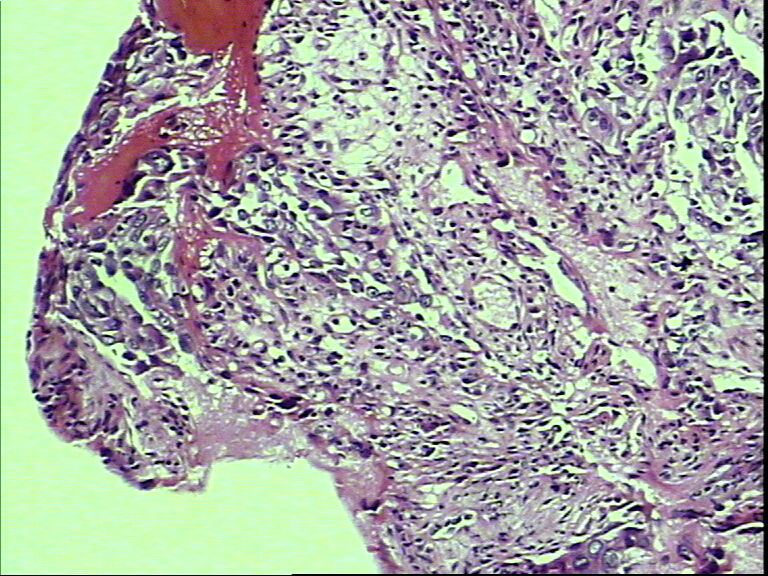

支气管活检,女性,65岁

• 支气管活检,女性,65岁图2

图2

鳞癌?腺癌?

鳞状细胞癌

组织太少,考虑鳞癌(建议再检)。

就本例而言基本肯定是鳞状细胞癌,退一步讲是腺癌的话,也不需再次活检了,排除小细胞癌了,不影响治疗方案了,只要其他情况还好的话,手术治疗是首选了。